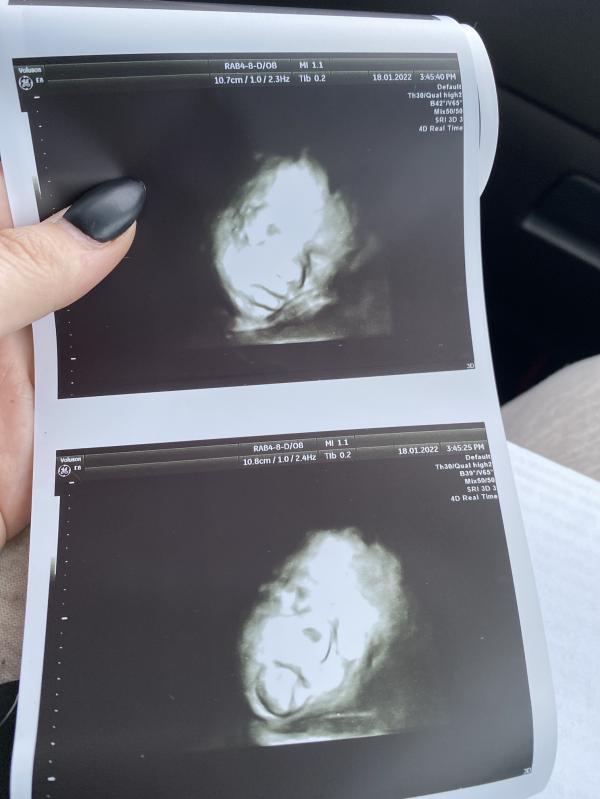

Дочь ещё не родилась, а уже имеет вредный характер овна😹 ходили сегодня на 3д узи и вот эта мадам закрыла своё личико ногами и рукой, отправили поболтаться по коридору, не помогло🥲 в итоге выпила сладкий кофе и съела маленькую шоколадку, буквально на минуты 3 мадмазель соизволила нам показаться и с первой секунды показала язык 😹🙈 потом приняла тоже положение) все же мы успели сделать годные снимочки) были в арнике у романовской 🥰

27 недель